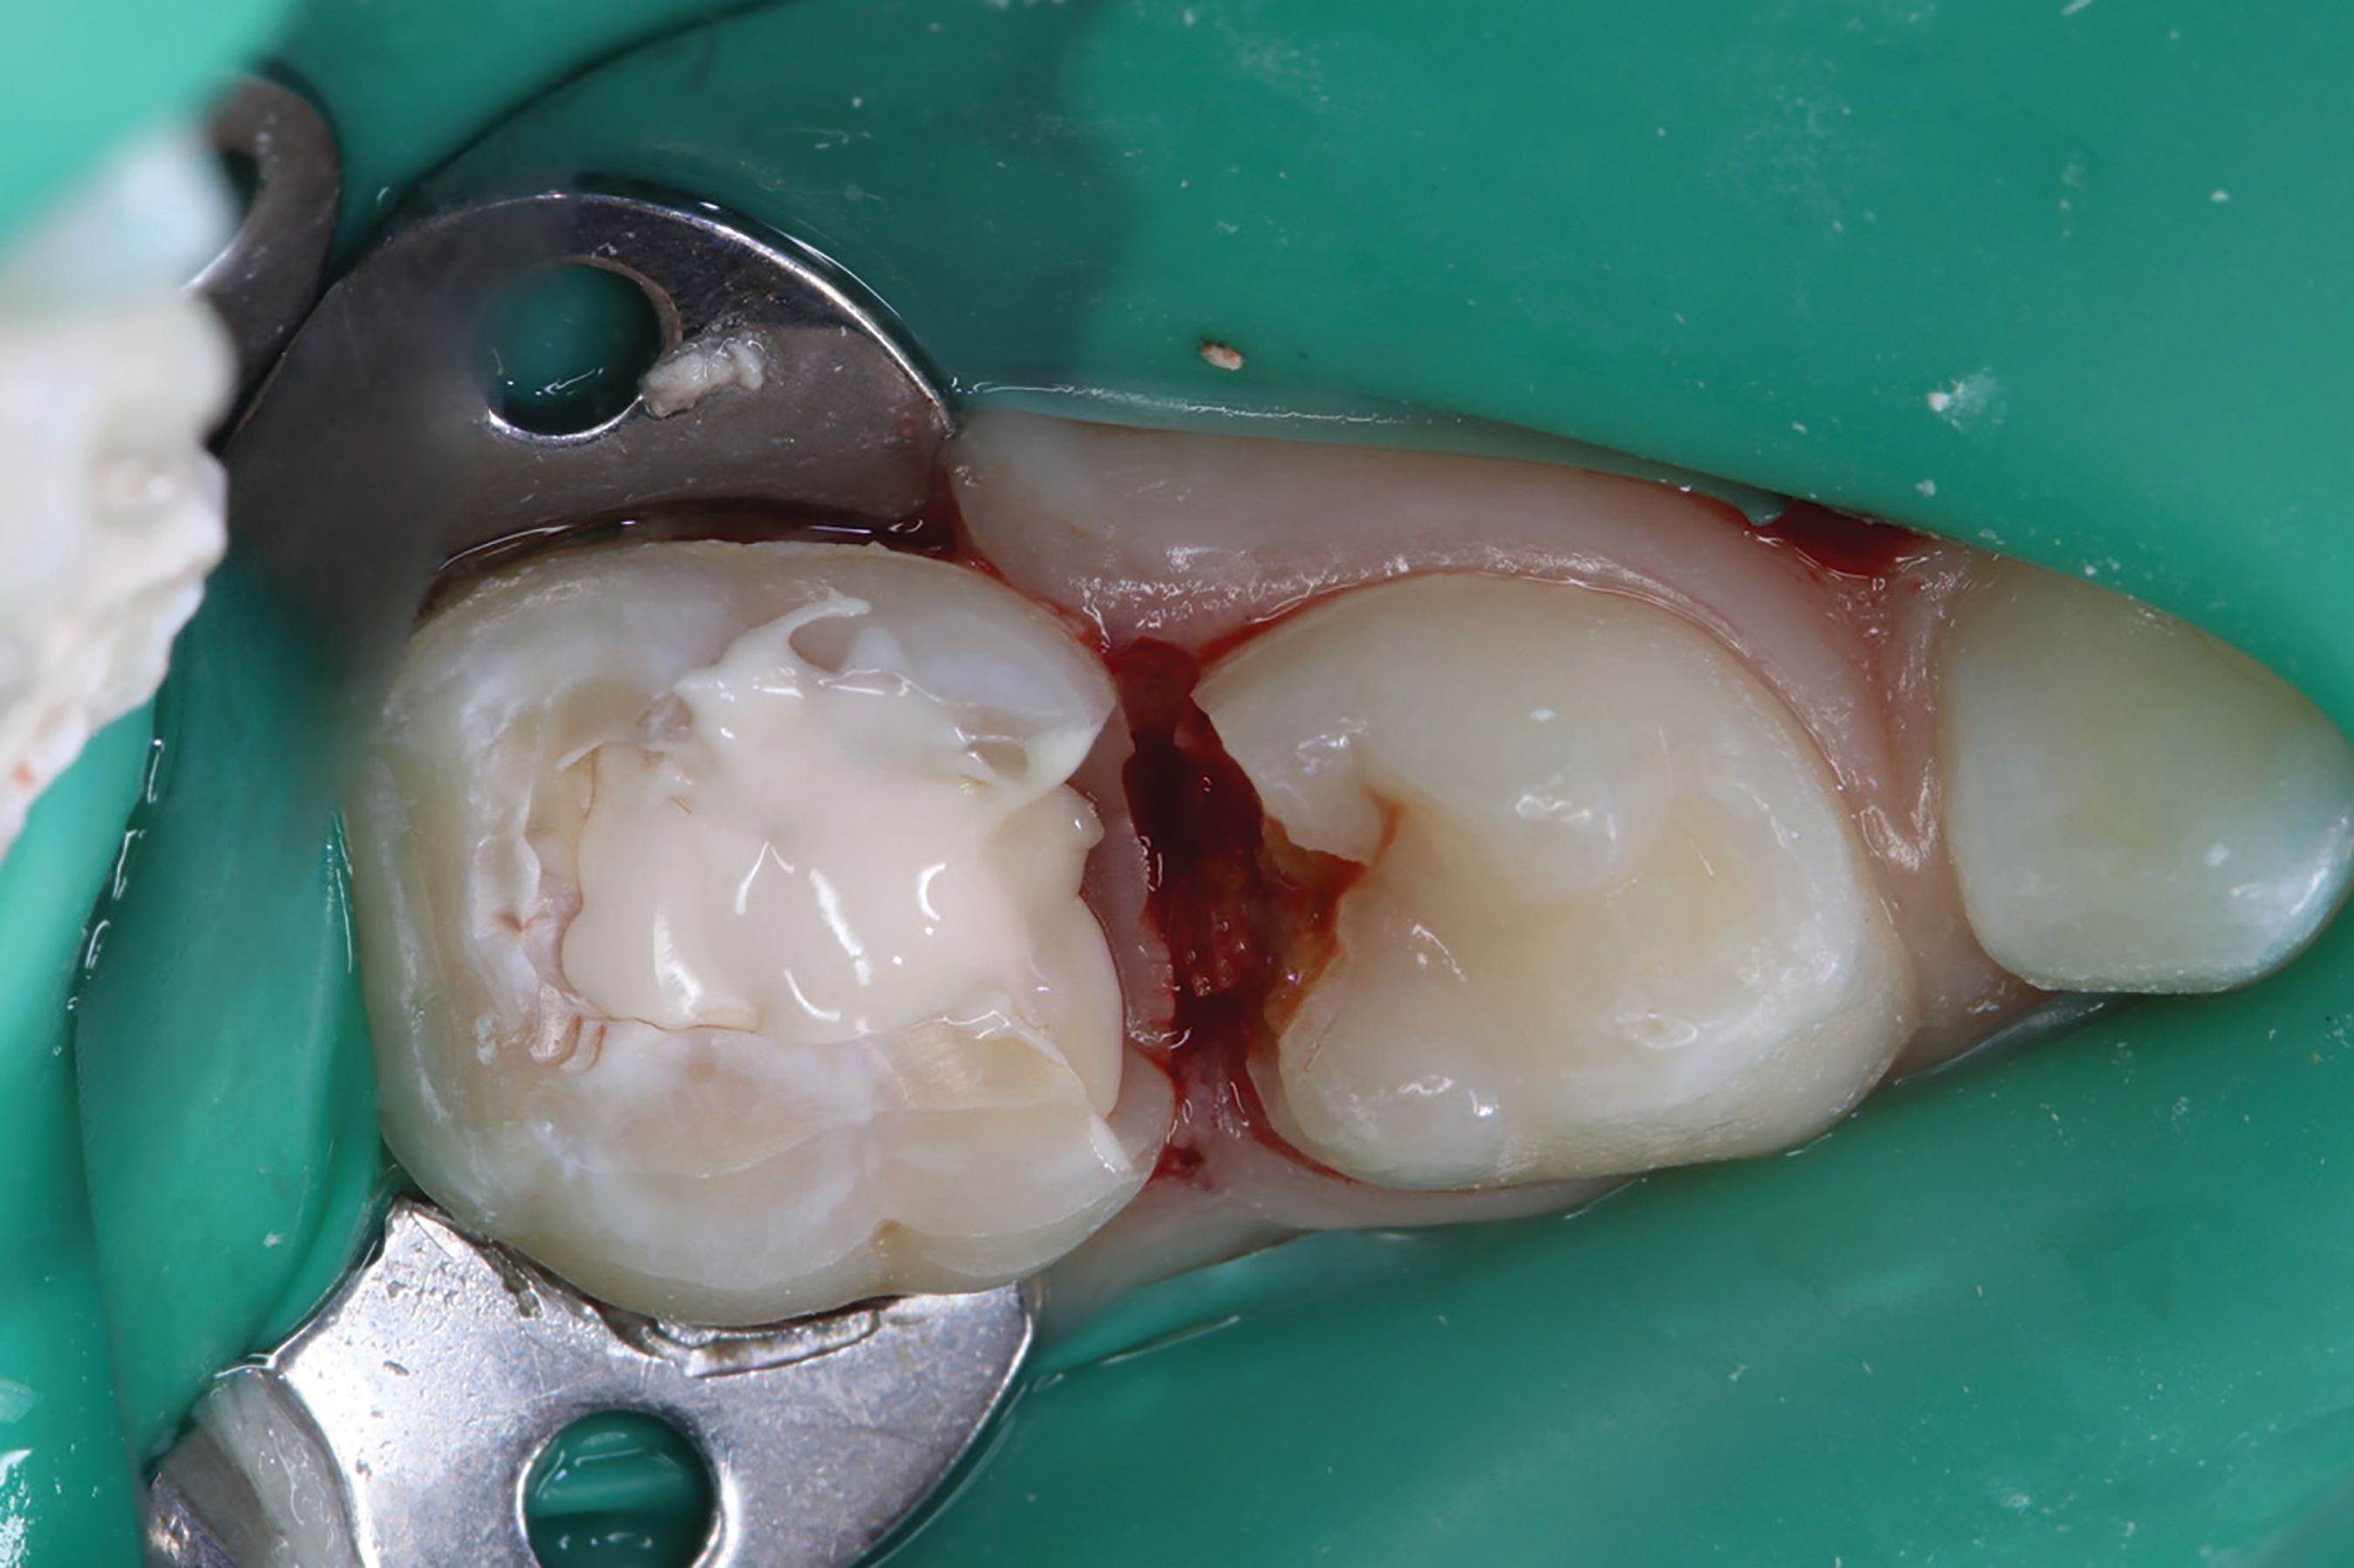

AT A GLANCE [ Figs. 1-9 ] Pre-operative view-primary second molar requiring pulpotomy procedure (Fig. 1). Amputation of coronal pulp chamber to level of radicular pulp stumps with NSK Dental’s slow speed large round bur #8, removing coronal pulp tissue with gentle upward motion (Fig. 2). Hemostasis achieved with saline-soaked sterile cotton pellet (Figs. 3 & 4). Hemostasis achieved (Fig. 5). Extrusion of TheraCal PT into pulp chamber, being sure to reach base of coronal pulp chamber with material and without voids or bubbles and light cure (Figs. 6 & 7). Cured TheraCal PT (Fig. 8). Full-coverage stainless-steel crown (Fig. 9).

Amputation of coronal pulp chamber to the level of radicular pulp stumps was performed with NSK Dental slow speed large round bur #8, removing coronal pulp tissue with gentle upward motion (Fig. 2). Hemostasis is achieved with a saline-soaked sterile cotton pellet (Figs. 3-4). Figure 5 also illustrates hemostasis.

Next came extrusion of TheraCal PT into the pulp chamber, being sure to reach the base of the coronal pulp chamber with material and without voids or bubbles and light cure (Figs. 6-7). Figure 8 shows cured TheraCal PT. The patient’s full-coverage stainless-steel crown (Fig. 9).